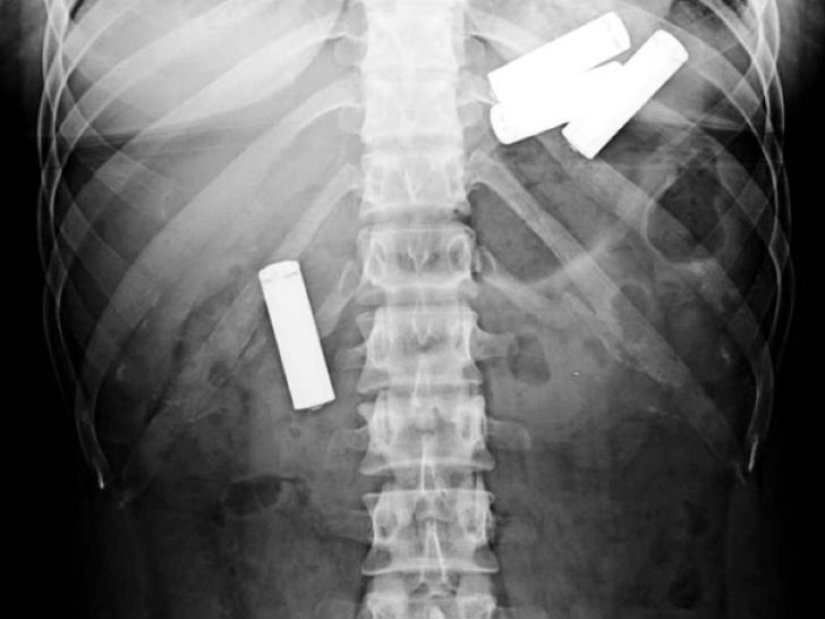

Here, perhaps, only children swallow batteries. X-ray of a 13-month-old baby.